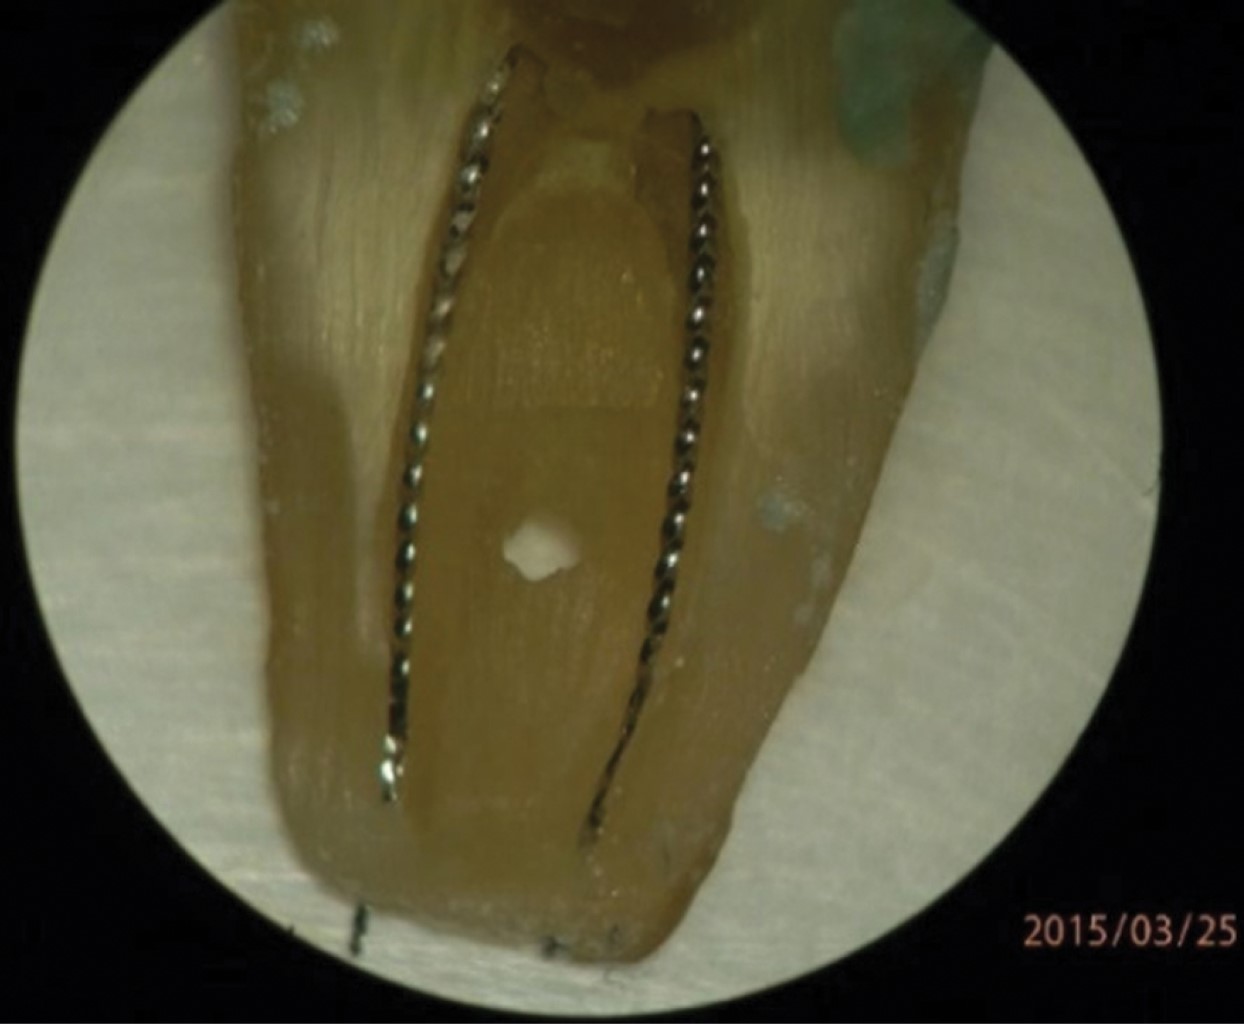

Un ejemplo de lo anterior se puede observar por medio de la técnica de pulpectomía lateral15 que muestra la posición de limas dentro de conductos MV y ML con salidas independientes en apical (Figura 11).